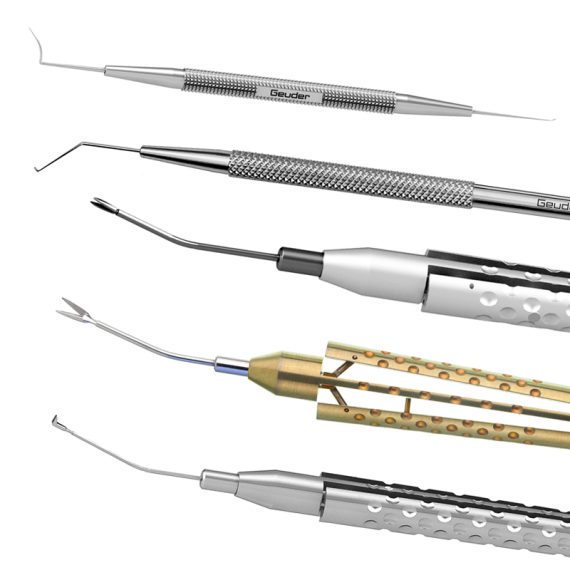

Geuder instrument rangeGeuder's instrument range delivers supreme quality and precision for...Code: Explore

Geuder instrument rangeGeuder's instrument range delivers supreme quality and precision for...Code: Explore -

Geuder NanoEdge™ knives rangeGeuder NanoEdge™ knives deliver exceptional sharpness and precision for...Code: Explore

Geuder NanoEdge™ knives rangeGeuder NanoEdge™ knives deliver exceptional sharpness and precision for...Code: Explore -

Stephens Instruments instrument rangeStephens Instruments delivers precision-crafted ophthalmic instruments for cataract, corneal,...Code: Explore

Stephens Instruments instrument rangeStephens Instruments delivers precision-crafted ophthalmic instruments for cataract, corneal,...Code: Explore -

Surgitrac instrument rangeSurgitrac offers a complete portfolio of high-quality ophthalmic instruments,...Code: Explore

Surgitrac instrument rangeSurgitrac offers a complete portfolio of high-quality ophthalmic instruments,...Code: Explore -